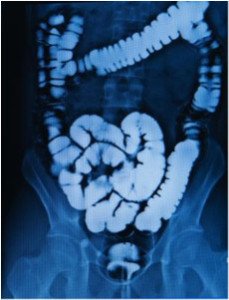

Enemas have been used for centuries to cleanse the colon. Simply an injection of liquid via the anus, enemas may help relieve constipation, gas and bloating, cleanse the colon and reduce the body’s toxic load. While the idea of giving yourself an at-home enema may seem like a daunting and uncomfortable task, it’s actually a very simple process that often feels more awkward than uncomfortable. Enema solutions can help with a variety of symptoms, using one of a variety of recipes.

10. Massage your abdomen in a counter-clockwise direction to assist the water to flow into the entire colon. When you’re ready to evacuate, get up and move to the toilet. You’ll want to stay close to a toilet for the next 30 to 60 minutes, as evacuating happens in stages.

As easy as at-home enemas are, it is not something that should be done when you have a list of things to accomplish during the same day. You’ll want to rest after your enema, drink plenty of hydrating fluids and maintain a diet of light meals that include nourishing, cooked foods, such as steamed vegetables, for the rest of the day. For general maintenance and colon health it is recommended that you give yourself an enema once a month. And although enemas are generally safe and complications are very rare in healthy adults, it is still recommended that you discuss appropriate enema solutions, precautions and even procedures with your naturopathic doctor before trying this at home.